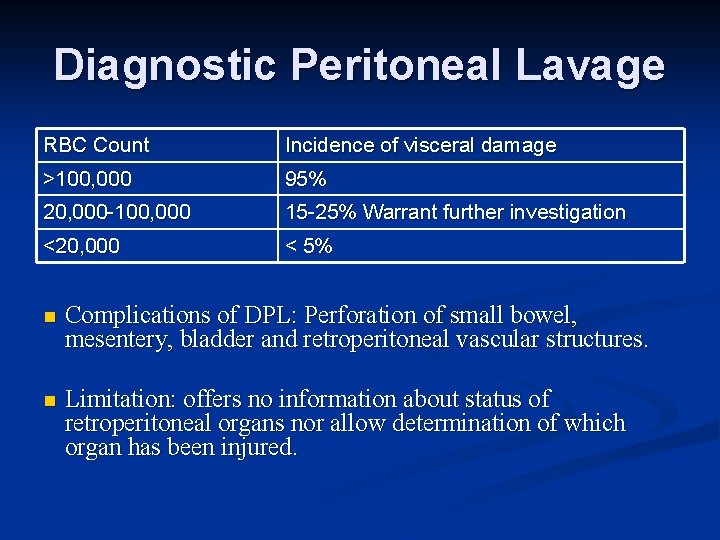

Diagnostic Peritoneal Lavage RBC Count Incidence of visceral damage >100, 000 95% 20, 000 -100, 000 15 -25% Warrant further investigation <20, 000 < 5% n Complications of DPL: Perforation of small bowel, mesentery, bladder and retroperitoneal vascular structures. n Limitation: offers no information about status of retroperitoneal organs nor allow determination of which organ has been injured.